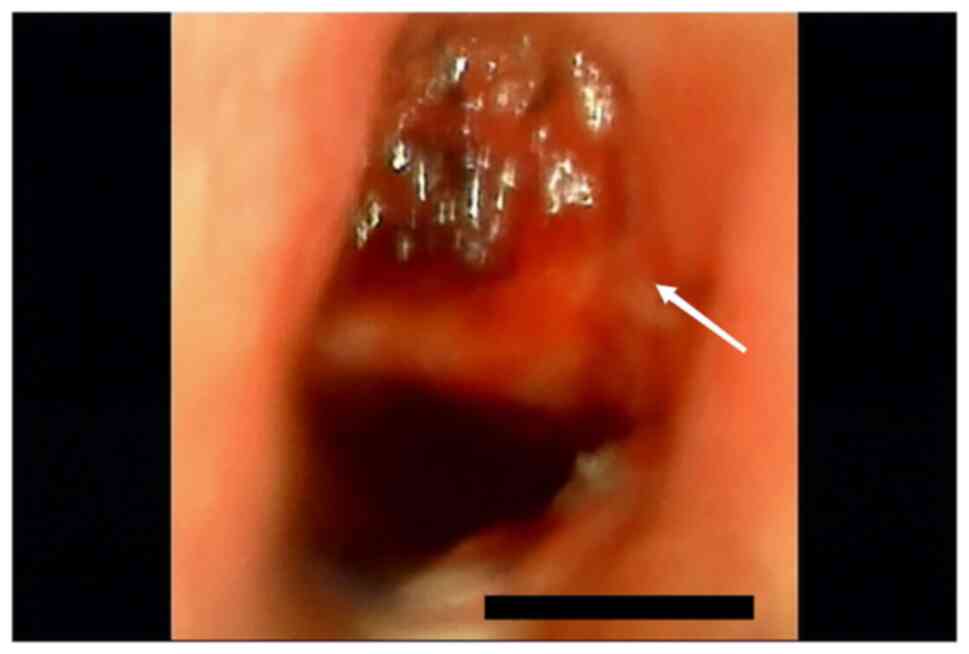

Figure 3

Image obtained during fiberoptic bronchoscopy. The white arrow indicates tracheal cartilage collapse and airway stenosis.

After ECMO decannulation, ventilator therapy was used under volume control mode (tidal volume, 8 ml/kg; respiratory rate, 25 breaths/min; positive end-expiratory pressure, 5 mmHg; oxygen concentration, 50%). Following the withdrawal of the ECMO machine, a chest CT was performed. Bilateral lung effusion and pleural effusion were reduced, and pneumothorax and subcutaneous emphysema was partially absorbed in the chest wall compared with the patient's condition at the time of admission. At 7 days after the injury, the patient's consciousness was similar to that on arrival at the trauma center, which may be related to craniocerebral injury or cerebral anoxia due to ventricular escape rhythm, and expectoration was poor. When the tracheal catheter was used for sputum aspiration, only ~20 cm of the sputum aspiration tube could be inserted. A fiberoptic bronchoscopy was performed and when the fiberoptic tracheoscope probe was inserted into the tracheal repair site, it was found that the tracheal cartilage had collapsed, resulting in airway stenosis (Fig. 3). In consultation with the Department of Otolaryngology, Jiaxing First Hospital, a tracheotomy was recommended. A tracheal tube was placed under the inferior tracheal cartilage through a median cervical incision. The patient was treated with high-flow oxygen therapy after tracheotomy and was then transferred to a general ward for rehabilitation. On the 10th day after injury, chest CT indicated that lungs were not compressed, and the pneumothorax and subcutaneous emphysema had been absorbed (Fig. 4). After 24 days of hospitalization, the patient's consciousness had improved; however, they could not take care of themselves. The patient was transferred back to the hospital of the first presentation, Jiashan First People's Hospital (Jiaxing, China), for rehabilitation treatment. The patient was discharged after 58 days of rehabilitation. In January 2023, the patient is off the ventilator, but is unconscious, bedridden and unable to care for themselves.